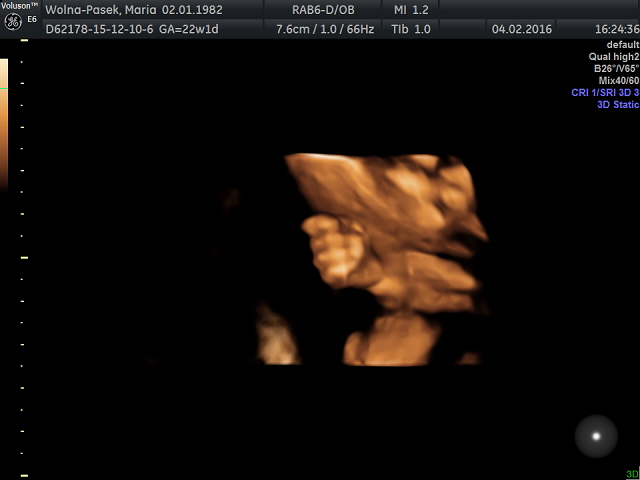

NASZE ZDJĘCIA

Po zakończonym badaniu otrzymałam jego wyniki na kartce, a zdjęcia i filmy Fasolki na pendrive – wszystkie możecie zobaczyć niżej.